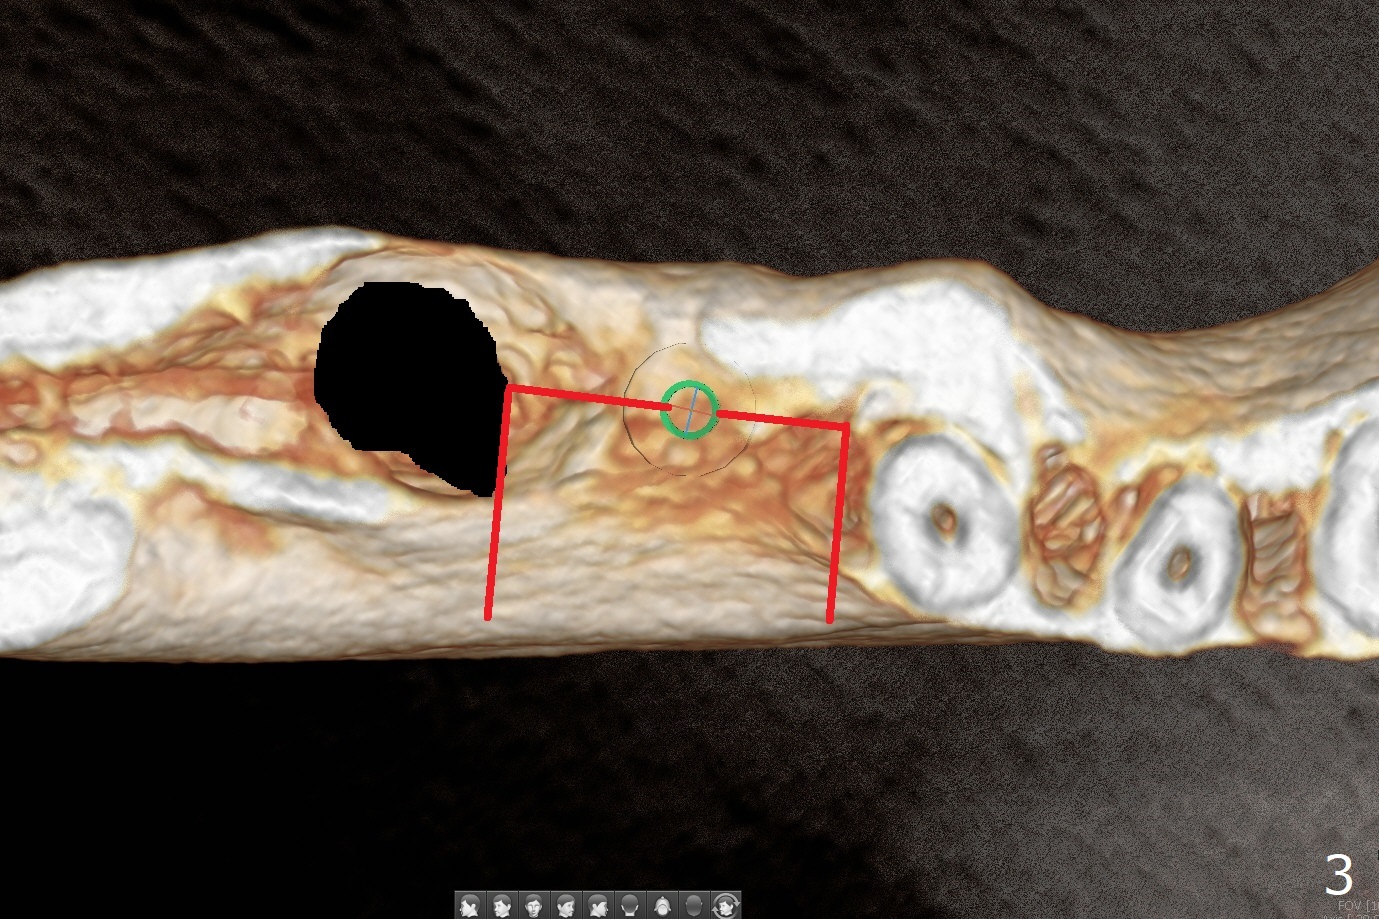

Several months post #31 socket preservation, the narrow ridge of #30 (Fig.1 (CT 3-D occlusal view), 6 (coronal section)) will be exposed with a crestal and 2 oblique incisions, followed by osteotomy with a 2 (2.2) mm drill (green) and a surgical guide. A crestal transverse cut will be conducted using a surgical fissure bur (Fig.2 red), followed by 2 vertical cuts (Fig.3,4 (3-D X-ray mode, buccal view) and an apical transverse one (Fig.5,6). The incision will be closed. Three weeks later, a crestal incision will be made. The buccal plate will be fractured and pushed buccal (Fig.7,8 arrow) using chisel (yellow). The guide will be reseated for osteotomy, implant placement (Fig.9 green) and bone graft. In fact there is not much problem when the osteotomy moves lingual.